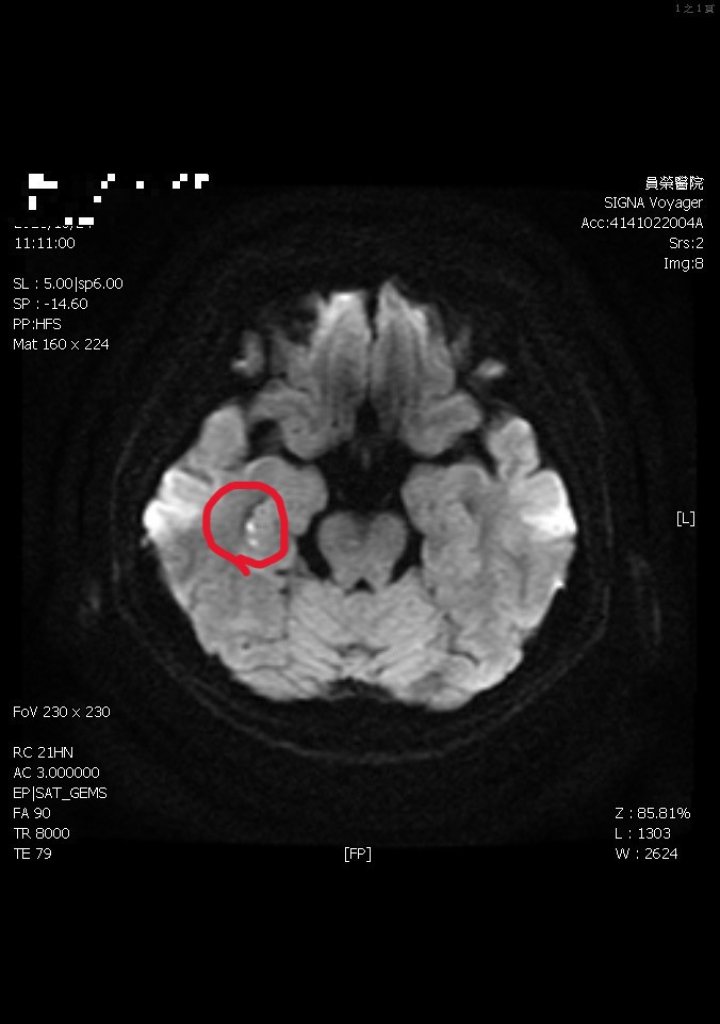

事故導致陳姓駕駛當場OHCA(到院前心肺功能停止),經緊急送往屏東榮民總醫院搶救後仍因傷重不治;另黎姓駕駛受輕傷,已送往屏東醫院接受治療。